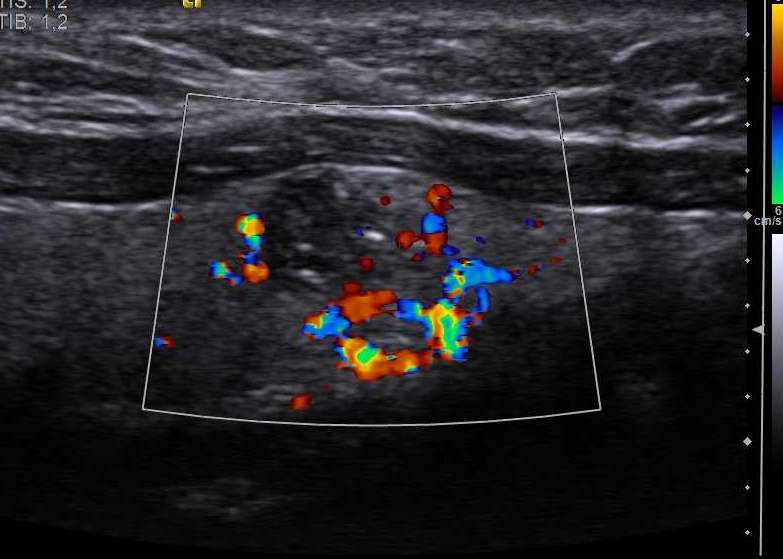

정기적인 건강 검진과 조기 발견 프로그램은 갑상선암의 예후를 크게 개선할 수 있습니다. 목을 촉진하여 비정상적인 성장이나 결절을 확인하고 초음파 검사를 실시하는 것은 간단하면서도 효과적인 검진 방법입니다.